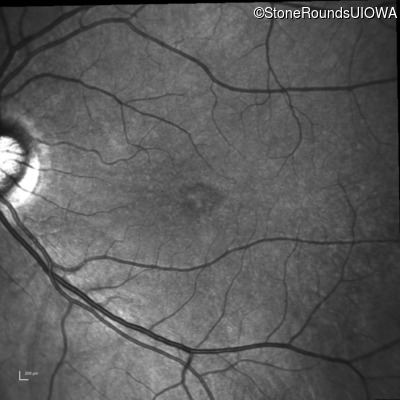

Infrared Fundus Photograph - Left - 20/40

Exemplar